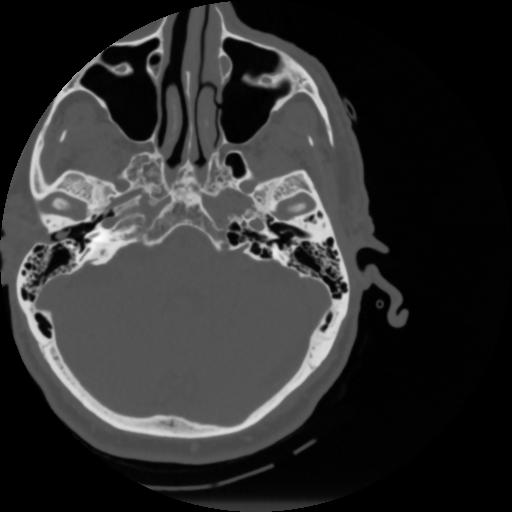

4 CEREBRO,,Vol,0.5,CEREBRO,,